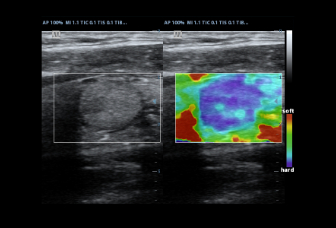

Пакеты плоскостей, охватывающие различные области применения: брюшная полость, акушерство и гинекология, щитовидная железа, молочная железа, яички.

Пакеты плоскостей, охватывающие различные области применения: брюшная полость, акушерство и гинекология, щитовидная железа, молочная железа, яички.